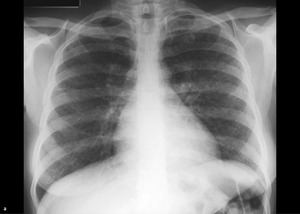

Rycina. (a) Zdjęcie RTG klatki piersiowej wykonane u 26-letniej kobiety z powodu suchego kaszlu wykazuje obustronne powiększenie węzłów chłonnych wnęk i okołownękowe miąższowe zmiany guzkowe. (b) Tomografia komputerowa lepiej uwidocznia guzki miąższowe rozmieszczone wokół naczyń limfatycznych oraz cechy zapalenia ziarniniakowego.